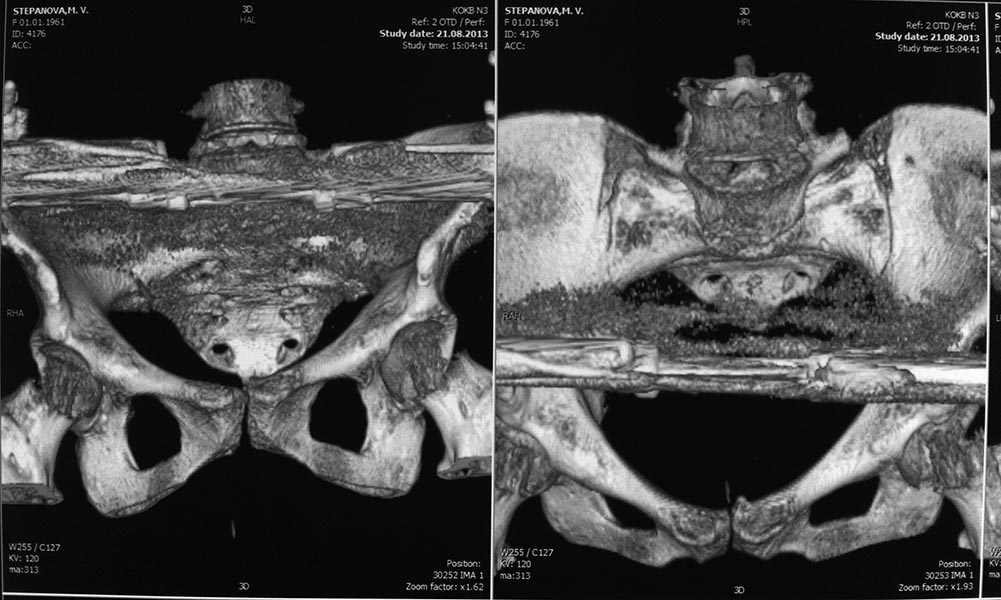

КТ, при детальном рассмотрении виден перелом задних отделов крыла подвздошной кости

KT